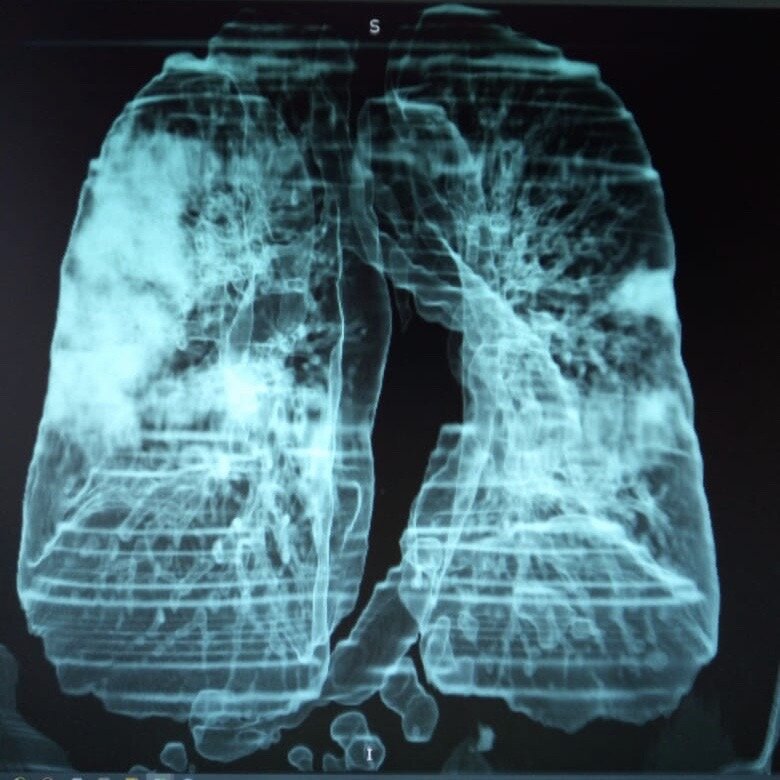

Как выглядит эффект на снимке

На рентгеновском снимке этот эффект выглядит следующим образом:

• наблюдаются обширные затемнения;

• на их фоне хорошо проглядывается структура бронхов и их стенки;

• легочная ткань становится более прозрачной;

• сосудистый рисунок сохраняется.

Вирусная пневмония на снимке КТ легких